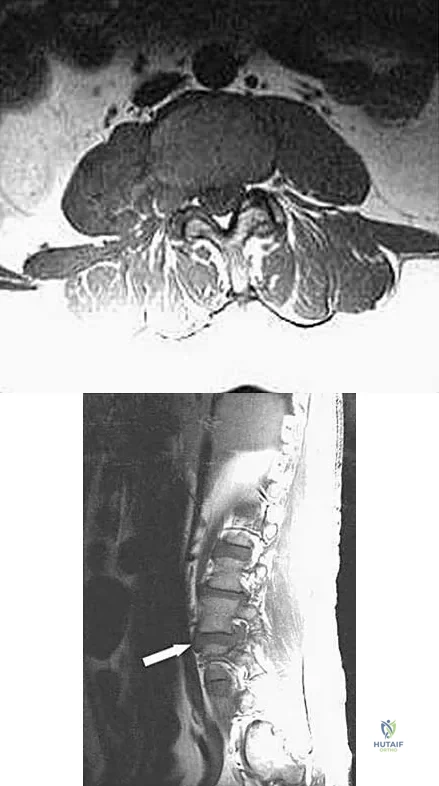

An otherwise healthy 45-year-old woman reports the onset of severe right leg pain. Figure 20a shows an axial MRI scan of the L4-5 level, and Figure 20b shows a sagittal view with the arrow at the L4-5 level. What nerve root is the most likely source of her pain?

Explanation

The scans show a disk herniation in the far lateral region of the disk. In particular, the sagittal view shows the herniation adjacent to the exiting L4 nerve root. Disk herniations in this area that cause symptoms are more likely to compress the nerve exiting at the same level rather than the next most caudal level. McCulloch JA: Microdiscectomy, in Frymoyer JW (ed): The Adult Spine: Principles and Practice. New York, NY, Raven Press, 1991, vol 2, pp 1765-1783.

- Hodges SD, Humphreys SC, Eck JC, Covington LA: The surgical treatment of far lateral L3-L4 and L4-L5 disc herniations: A modified technique and outcomes analysis of 25 patients. Spine 1999;24:1243-1246.